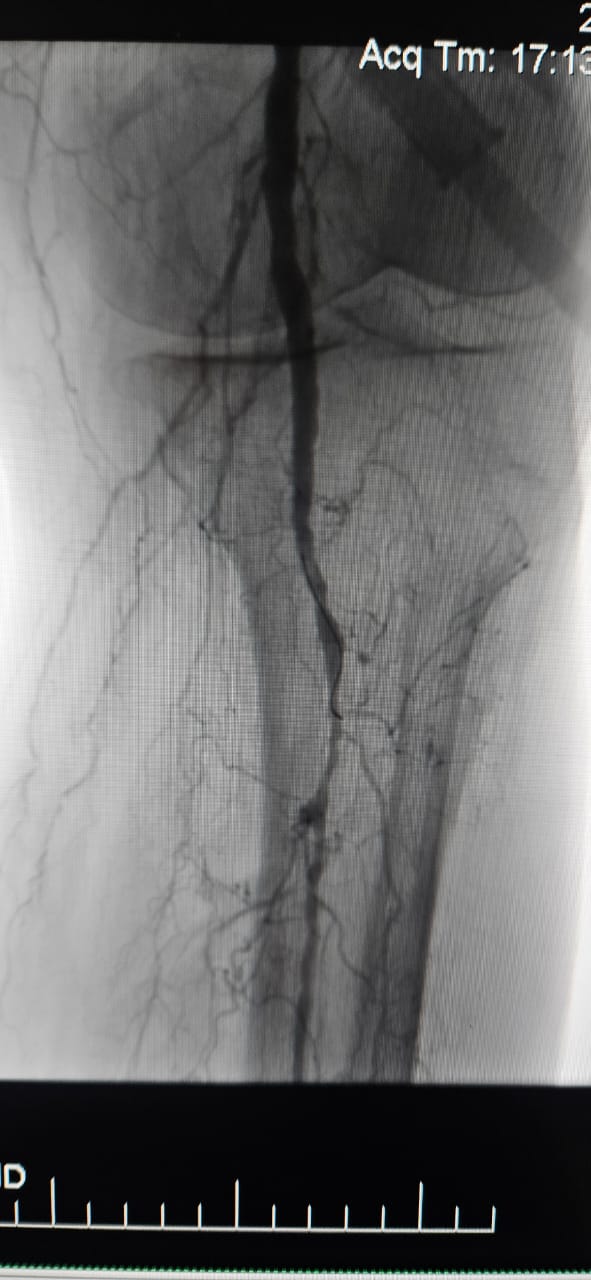

Мы рады поделиться успешным случаем из больницы в Батуми, Грузия, где 78-летняя пациентка с критической ишемией конечностей (CLI), вызванной хронической полной окклюзией артерии нижней конечности, показала значительное клиническое улучшение после лечения с помощью периферийной системы расширенного баллона ThorCrack IVL.

Этот случай подчеркивает клиническую ценность внутрисосудистой литотрипсии (IVL) в лечении сложных случаев CLI с хронической окклюзией длинного сегмента-особенно у пациентов с тяжелой кальцификацией, где традиционные баллоны или устройства для атерэктомии могут иметь ограниченную эффективность.

Мы гордимся тем, что ThorCrack IVL дает возможность врачам по всему миру преодолевать кальцинированные поражения, восстанавливать перфузию и улучшать результаты лечения пациентов при сложных заболеваниях периферических артерий.